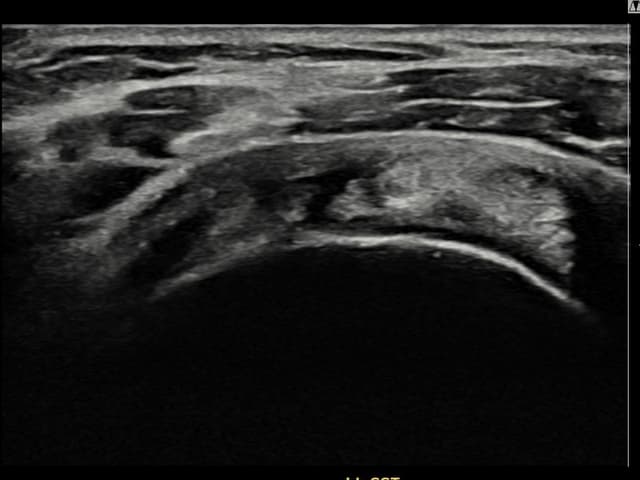

[촬영시기:22.09.06]

[석회분쇄흡입술] 좌측 어깨 통증으로 팔을 옆으로 올리기 어려워진 60대 남성 환자로, X-ray에서 좌측 극상근건 내 석회 침착이 확인되어 석회분쇄흡입술을 시행하였습니다.